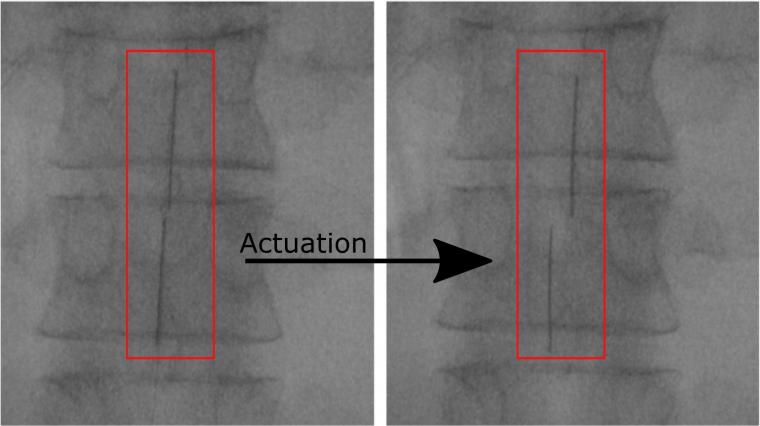

Όταν βρεθεί μέσα στο σώμα, η συσκευή φουσκώνει με νερό ή αέρα και ξετυλίγεται σαν ένα μικρό στρώμα που καλύπτει ένα μεγάλο τμήμα του νωτιαίου μυελού. Όταν συνδέεται με μία γεννήτρια παλμών, τα ηλεκτρόδια της συσκευής αρχίζουν να στέλνουν ηλεκτρικά σήματα στον νωτιαίο μυελό, μπλοκάροντας τα σήματα του πόνου.

Οι έως τώρα συσκευές μπλοκαρίσματος του νωτιαίου μυελού κατά του πόνου είναι ογκώδεις και απαιτούν επεμβατικό χειρουργείο, γι’ αυτό μόνο 50.000 τέτοιες επεμβάσεις γίνονται κάθε χρόνο παγκοσμίως (η σχετική θεραπεία θεωρείται ως μέτρο τελευταίας καταφυγής για όσους ασθενείς νιώθουν πολύ σοβαρούς και μη αντιμετωπίσιμους πόνους). Η νέα συσκευή είναι πολύ πιο μικρή σε μέγεθος (έχει πάχος μόλις 60 εκατομμυριοστά του μέτρου) και είναι πιο εύκολο να εισαχθεί στο σώμα.

Οι έως τώρα δοκιμές δείχνουν ότι η καινοτόμος συσκευή μπορεί να αποτελέσει μία αποτελεσματική θεραπεία για πολλές μορφές σοβαρού πόνου, όπως στα πόδια και στη μέση, που δεν μπορούν να αντιμετωπιστούν με αναλγητικά. Επίσης, θα μπορούσε πιθανώς να προσαρμοστεί για να αποτελέσει μία νέου τύπου θεραπεία της παράλυσης ή της νόσου Πάρκινσον.